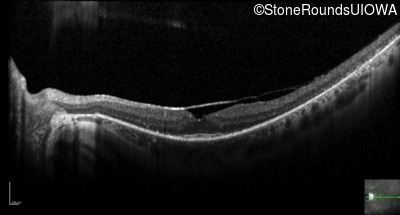

Optical Coherence Tomography - Right - 20/25 -3

Exemplar / OCT Stack